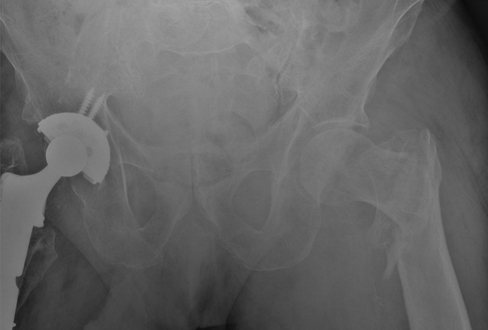

与患者和家属讨论后,他们希望继续进行非手术措施以促进骨折愈合。初次受伤后4个月的连续影像学检查显示,骨折已经愈合。